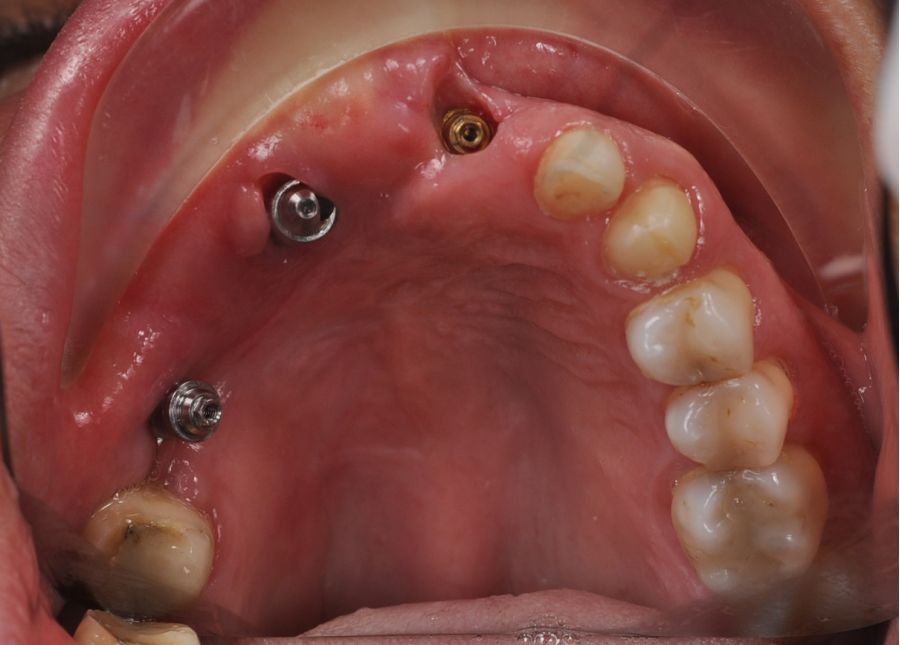

Bajo anestesia general, se realizó la resección quirúrgica junto con la fijación de dos placas preformadas y colocación simultánea de dos implantes cigomáticos y un implante endoóseo en posición del 2.1 (Figuras 5 y 6). Debido a la presencia de márgenes quirúrgicos comprometidos en el informe anatomopatológico, se indicó la administración de radioterapia adyuvante. Por este motivo, se decidió realizar un puente provisional dentosoportado de 1.7 a 2.3 (Figura 7) para mejorar la situación estética y funcional de la paciente durante todo el proceso y evitar un colapso de los tejidos blandos por la radioterapia. Para ello, se tallaron los molares (1.7, 1.6) e incisivo lateral y canino (2.2, 2.3), y se fabricó un puente fresado en polimetilmetacrilato (PMMA) con refuerzo metálico (Figuras 8 y 9).

Una vez finalizada la radioterapia, la paciente se encontraba libre de enfermedad. Por lo que se procedió a la restauración definitiva implantosoportada. Tras la segunda fase, se colocaron dos pilares transepiteliales Multiunit Ò rectos y un pilar Multunit Ò angulado de 17º (Figura 10).